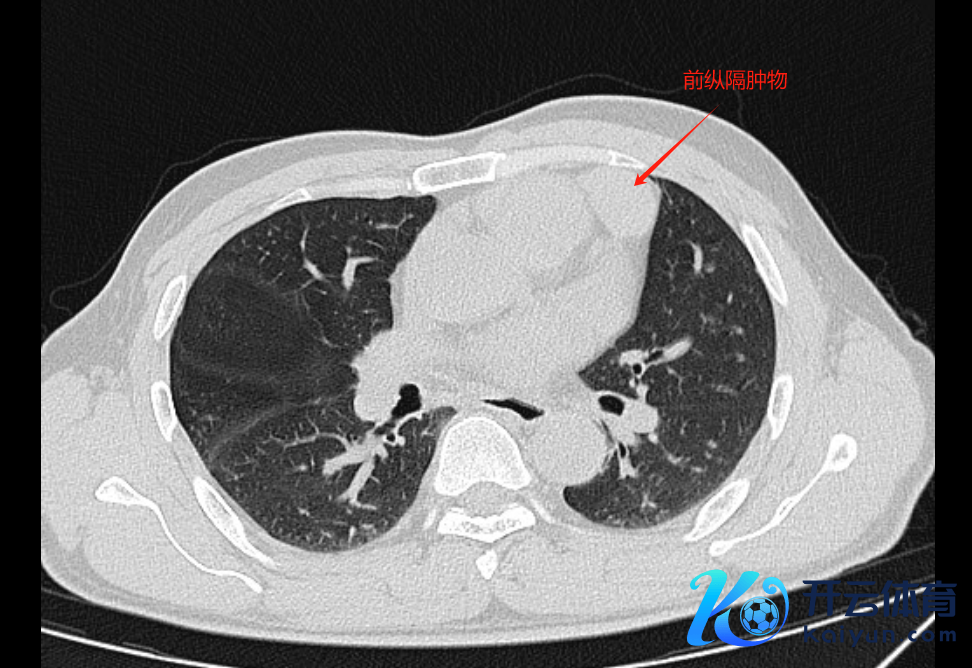

患者因左侧前纵隔发现一个大小约为33mm×29mm的肿块而住院。经由MRI检查,初步会诊为胸腺肿瘤。居然主任联结术前影像贵寓,有计划到肿瘤位于腹黑与胸壁之间相称细小的空间内,而且与心包紧密邻接,如若遴荐传统的开刀手术面貌,可能会加多风险。因此,为了确保手术的安全性及有用性,给患者制定了机器东谈主胸腔镜下纵隔肿物切除的手术有臆度打算。